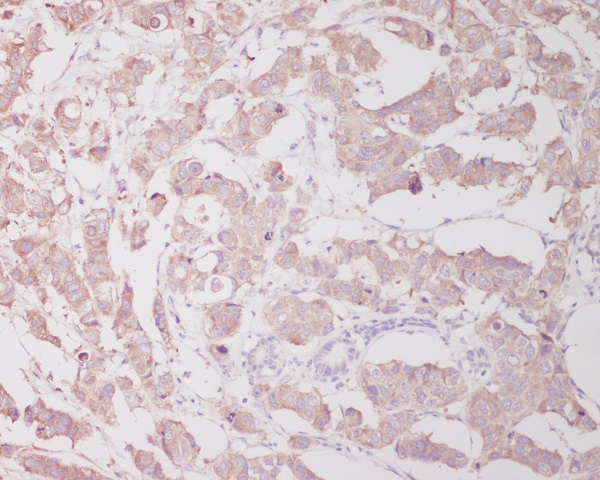

Immunohistochemical analysis of paraffin-embedded human breast cancer, using Beclin 1 Antibody.